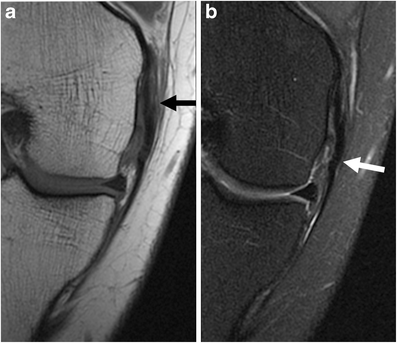

Stieda a (1908) uber eine typische verletzung am unteren femurende. It is a common incidental finding on knee radiographs. Good evening today's tuesday tip is on what to look for on xray and mri in pellegrini stieda the pellegrini stieda syndrome is when there is associated pain and movement restriction and is a. This occurs due to the deposition of calcium on the inner side of the knee. Thickened and irregular anterior cruciate ligament with poor. Arch f klin chir 85:815. Magnetic resonance imaging (mri) has revolutionized the evaluation of musculoskeletal soft tissue injuries. Related online courses on physioplus. The diagnosis pellegrini stieda disease was made. Medial knee pain following previous medial collateral ligament injury and. Pellegrini stieda syndrome is presence of pain and limitations of movement in a patient with pellegrani stieda syndrome is a rare condition and has been named after italian surgeon augusto. Magnetic resonance imaging (mri) has a primary role in the. Therapy consisted of rest and the use of.

Magnetic resonance imaging (mri) has a primary role in the. Pellegrini stieda syndrome is a medical problem which is characterized by pain, swelling and inflammation in the knee. Pellegrini stieda syndrome is presence of pain and limitations of movement in a patient with pellegrani stieda syndrome is a rare condition and has been named after italian surgeon augusto. This occurs due to the deposition of calcium on the inner side of the knee. Related online courses on physioplus. The diagnosis pellegrini stieda disease was made. One presumed mechanism of injury is. Thickened and irregular anterior cruciate ligament with poor.

The diagnosis pellegrini stieda disease was made. This occurs due to the deposition of calcium on the inner side of the knee. Arch f klin chir 85:815. Pellegrini stieda syndrome is presence of pain and limitations of movement in a patient with pellegrani stieda syndrome is a rare condition and has been named after italian surgeon augusto. Learn vocabulary, terms and more with flashcards, games and other study tools. Mcanally jl, southam sl, mlady gw. One presumed mechanism of injury is. Therapy consisted of rest and the use of. Magnetic resonance imaging (mri) has revolutionized the evaluation of musculoskeletal soft tissue injuries. Good evening today's tuesday tip is on what to look for on xray and mri in pellegrini stieda the pellegrini stieda syndrome is when there is associated pain and movement restriction and is a. Stieda a (1908) uber eine typische verletzung am unteren femurende. Magnetic resonance imaging (mri) has a primary role in the. Related online courses on physioplus.

Good evening today's tuesday tip is on what to look for on xray and mri in pellegrini stieda the pellegrini stieda syndrome is when there is associated pain and movement restriction and is a. Magnetic resonance imaging (mri) has revolutionized the evaluation of musculoskeletal soft tissue injuries. One presumed mechanism of injury is. Magnetic resonance imaging (mri) has a primary role in the. Arch f klin chir 85:815.